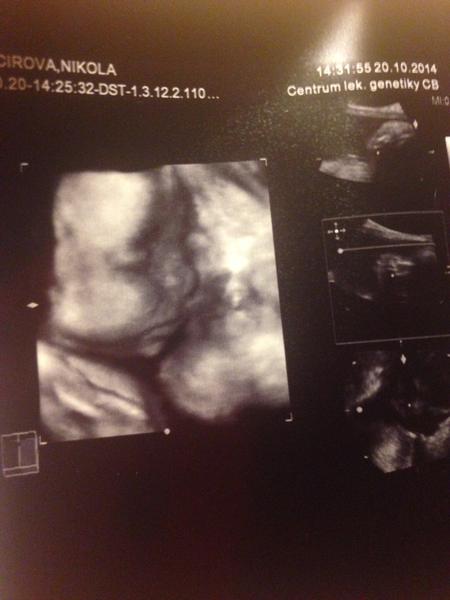

@tercasv ony ty cizí fotky na internetu jsou něco jiného, než když pak člověk vidí toho svého cvrčka 🙂 Mě tedy zase tak moc neoslovily přímo ty fotky - byť se nám povedly docela hezky, ale líbil se mi ten zážitek. Je vidět, jak se tam miminko tváří, jak zívá, dělá ksichtíky........🙂

Za mě fajn cesta do hlubin ...maminčina bříška - moc me bavilo, když jsem pak našla fotku ze 3D a fotku reálnou, které byly témeř totožné - tvář, výraz......

Musím říct, že to bylo super. Přesto, že nejsem zrovna hubená a mám placentu na přední straně, tak bylo mimčo krásně vidět. Oproti těm skoro mazaninám od gynekologa nesrovnatelné....

@tercasv Ja od toho moc neocekavala, premluvil me manzel, ze to zkusime, ze bychom treba litovali. Malej se nechtel ukazat oblicejem, takze jsme si dobre prohledli jeho zadek a naprosto presne vedeli, ze to bude kluk🙈 Pak se ale ukazal a stalo to za to. Mam fotku, kterou mam stale vytavenou na stole a rada se koukam, jak si byl po narozeni podobny, vcetne jeho mimiky😀 U me to tedy predcilo ocekavani, nejen ten vysledek, ale i ten zazitek byl fajn😀.

Stojí - ale až tak v tom cca 23-28 týdnu 🙂 to už je krásně vidět obličejík. Já mám od dcery i syna i moc pěkná videa 🙂